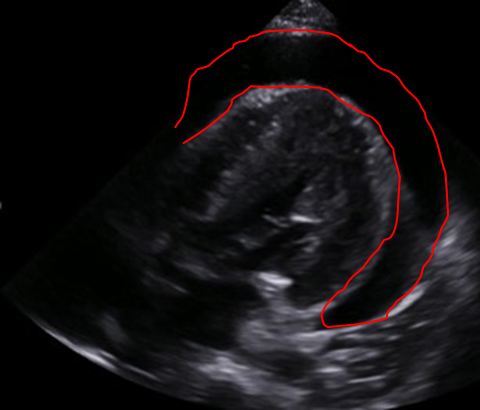

Img | CXR: cardiomegaly Echo: large circumferential pericardial effusion |

저혈압, 경정맥 확장, 심음 저하가 있고 심초음파에서 대량의 심낭 삼출이 보이므로 심장눌림증으로 진단하며 응급 심낭 천자를 시행한다.

• 시행한 심초음파에서 pericardial effusion이 다량으로 확인된다. 심장눌림증으로 진단하며, 응급처치로 초음파 유도 심장막천자로 감압한다.